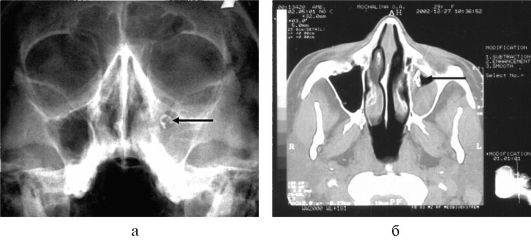

Если лечение не начато вовремя, заболевание может перейти в хроническую форму, что может потребовать хирургического вмешательства. Однако перед операцией необходимо будет провести компьютерную томографию.

Методы диагностики полипозного риносинусита

Чтобы точно определить вид болезни и степень поражения носовых пазух, используются такие методы:

- Компьютерная томография.

- Рентгенография.

- Эндоскопия.

Наиболее точную картину о патологии дает эндоскопическое исследование. Эта процедура относится к малоинвазивным, но при этом позволяет детально и точно исследовать слизистую носа и ткани носовых полостей. Проводится она с использованием специального прибора – эндоскопа.

Назальный эндоскоп представляет собой тонкую трубку из жесткого материала, внутри которой находится волоконно-оптический кабель. Через него исследуются под разными углами все участки поверхности носовых проходов и устанавливаются малейшие разрастания и новообразования.

Полученная информация передается на монитор, затем фиксируется и распечатывается. Эндоскопия носовых полостей делается несколько раз, пока проводится лечение – это позволяет отследить динамику и при необходимости откорректировать программу терапии. На данный момент это самый эффективный метод диагностики полипозного риносинусита.